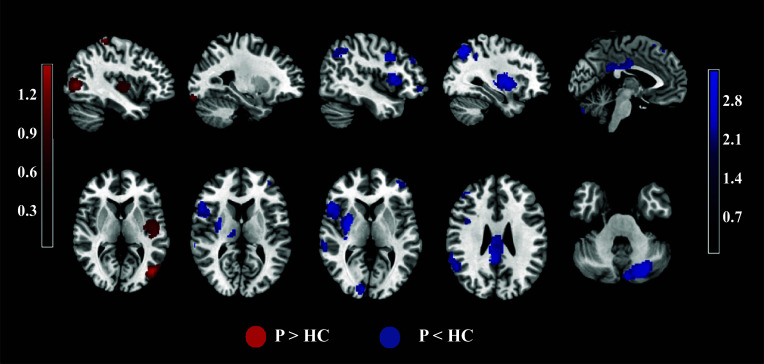

Study results: Patients with psychosis presented increased activation in the left middle occipital gyrus, insula, and lingual and postcentral gyri; decreased activation in cortico-striato-thalamo-cortical (CSTC) networks, including the dorsal striatum, insula, thalamus, middle cingulate cortex, posterior cingulate cortex, dorsolateral, orbital, and medial prefrontal cortices (DLPFC, OFC, and mPFC), cerebellum, and associated sensory areas, during instrumental learning. Moreover, mPFC hypoactivation was negatively associated with the percentage of first-generation antipsychotic users, and insula hyperactivation was negatively associated with the percentage of medicated individuals.

Conclusions: Our study revealed that the CSTC circuit could facilitate action-based reward learning in psychosis and may help explain the neuropathological mechanisms underlying these deficits in this disorder.